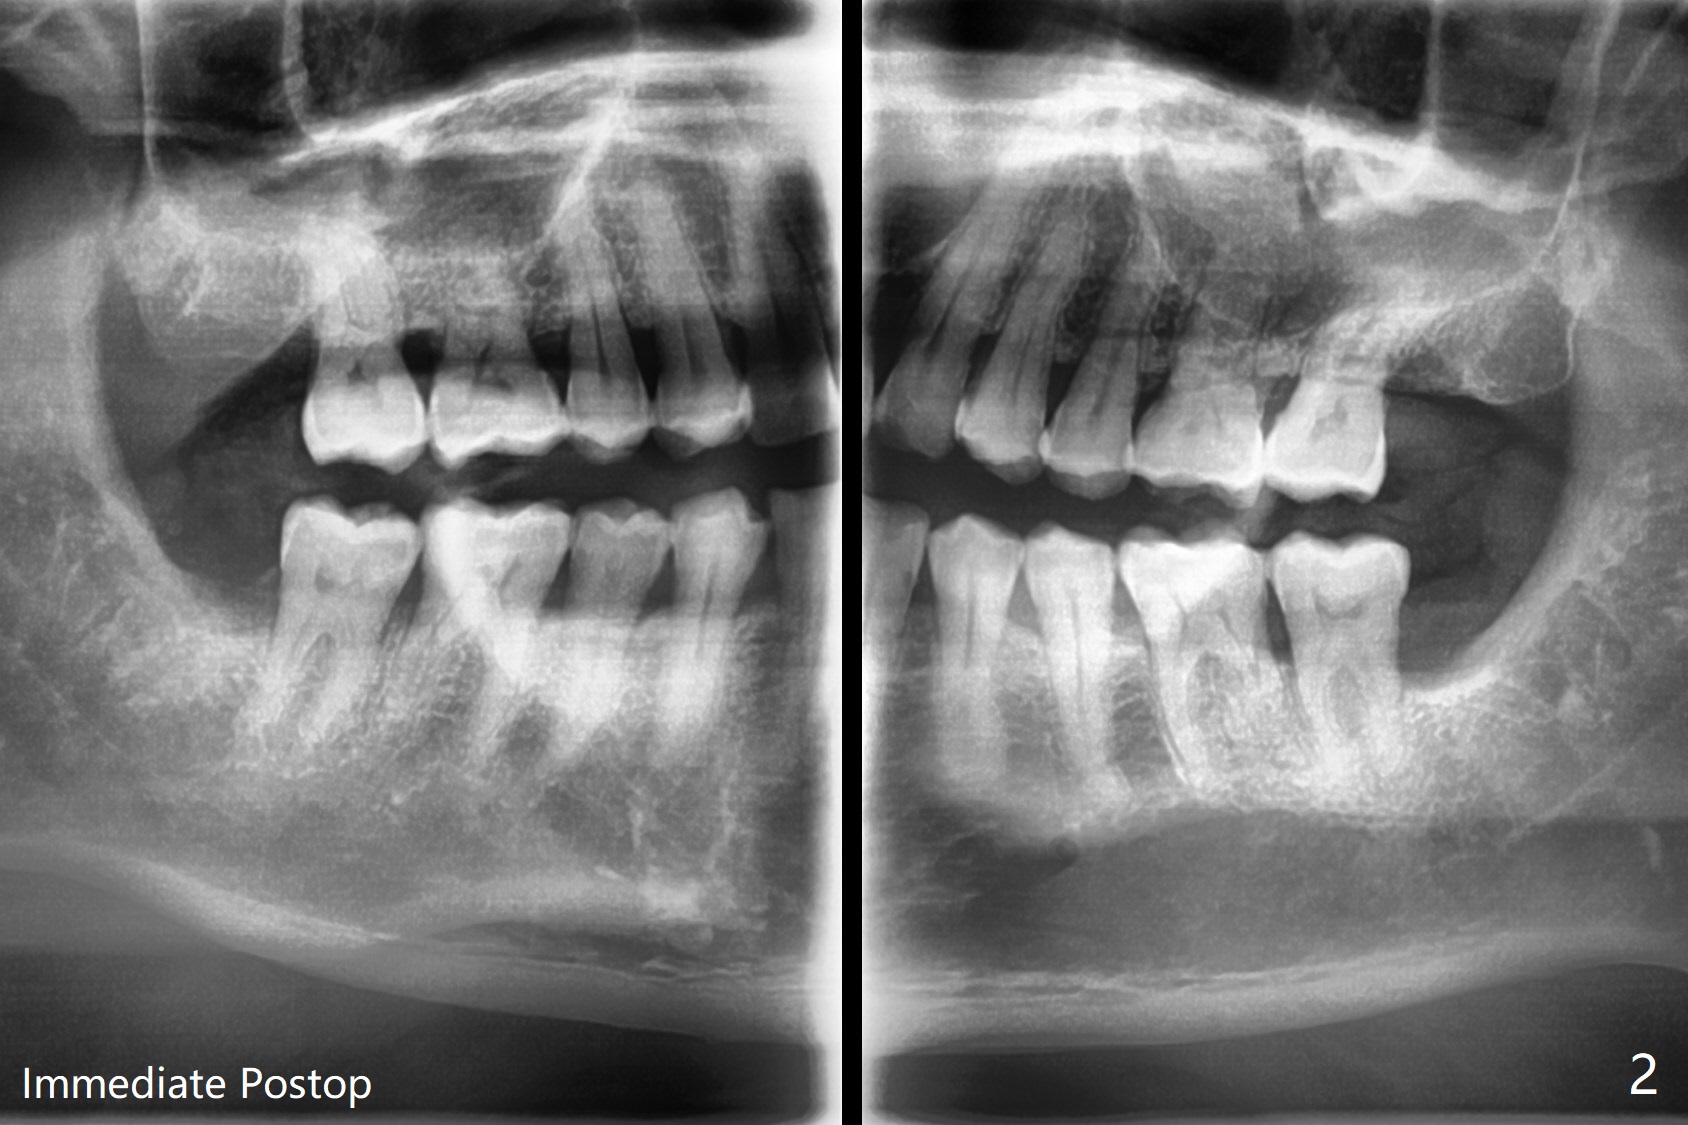

A 55-year-old man, smoker 1/2 ppd, has chronic periodontitis with heavy calculus between #17 and 18 (Fig.1). Six month post SRP, one piece of Osteogen plug is placed in each socket of #17 and 32 to promote bone growth and prevent dry socket (Fig.2). The bone is dense; the teeth needs sectioning several times before extraction.